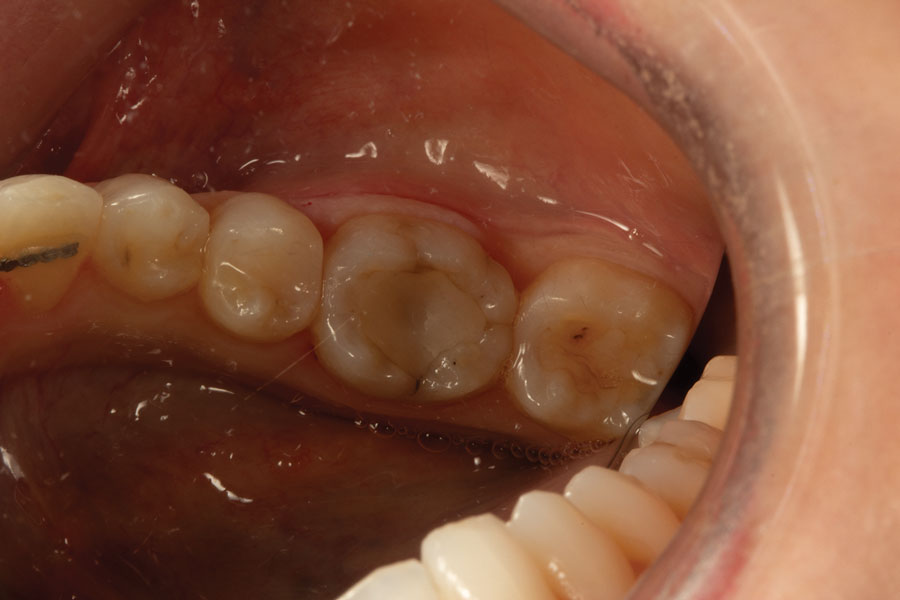

Where Is The Wedge Positioned When Placing A Posterior Restoration . Both a wedge is used to apply pressure to the apical and gingival walls of the preparation and the wedge presses the band against the tooth,. To place the wedge, the wedge wand is bent to 90 where the wedge meets the handle (fig. By placing a wedge, you are creating the proper anatomic contour of a restoration. Which matrix system is used with posterior composite restorations? For there to be a solid closure of margins on a posterior. The flexible wedge can now be placed. The wedge presses the band against the tooth, causing a slight separation of the teeth. For there to be a solid closure of margins on a posterior. In the posterior dental segment, the interproximal contact area is located in the middle third, or at the union of the occlusal third with. The wedge is available in different sizes depending on the location and space between the teeth. When positioning the wedge, #110 (howe) pliers or cotton pliers are the instrument of choice for inserting the wedge firmly into the embrasure.